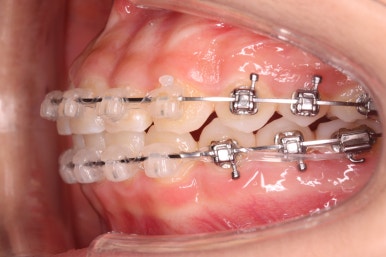

윗니에도 이제 장치를 모두 붙였습니다. 아래쪽은 어느 정도 가지런해지고 나면 부족한 자리를 만들어주기 시작합니다.

부산치아교정잘하는곳 키다리아저씨치과에서 이번 환자분에 사용한 장치는 데이몬 클리어라고 하는 세라믹 자가결찰 장치입니다. 세라믹 자가결찰 장치 중에서 철사를 잡아주는 CAP 부위까지 세라믹으로 되어있어 가장 심미적인 장치라고 볼 수 있습니다.

특히 웃을 때 철사 이외에는 장치가 크게 눈에 띄지 않아서 심미성을 원하시는 분들이 많이 선택을 하는 장치입니다.

다만, 약간 부피감이 있다보니 장치 부착 후 약간 입술 돌출감이 느껴지기도 하는데요. 장치 부착 전후로 옆모습을 비교해보겠습니다.

장치의 부피감으로 인해 약간의 돌출되는 느낌은 느껴지지만 그에 비해 압도적으로 치아색에 가까운 장점도 있어 장단점을 비교해보시고 장치를 선택하시면 되겠습니다.

예상한대로 자리만 충분히 마련해주니 그동안 나오지 못하고 막혀있던 치아가 슬그머니 고개를 내밀고 있습니다.

좀 더 기다렸다가 좀 더 올라오면 장치를 부착해서 정리해주기만 하면 되겠습니다.

부산치아교정잘하는곳 키다리아저씨치과에서는 치아가 올라오자마자 장치를 부착하여 가지런하게 해줍니다. 이제 어느 정도 큰 그림은 그려졌다고 보시면 되겠습니다.